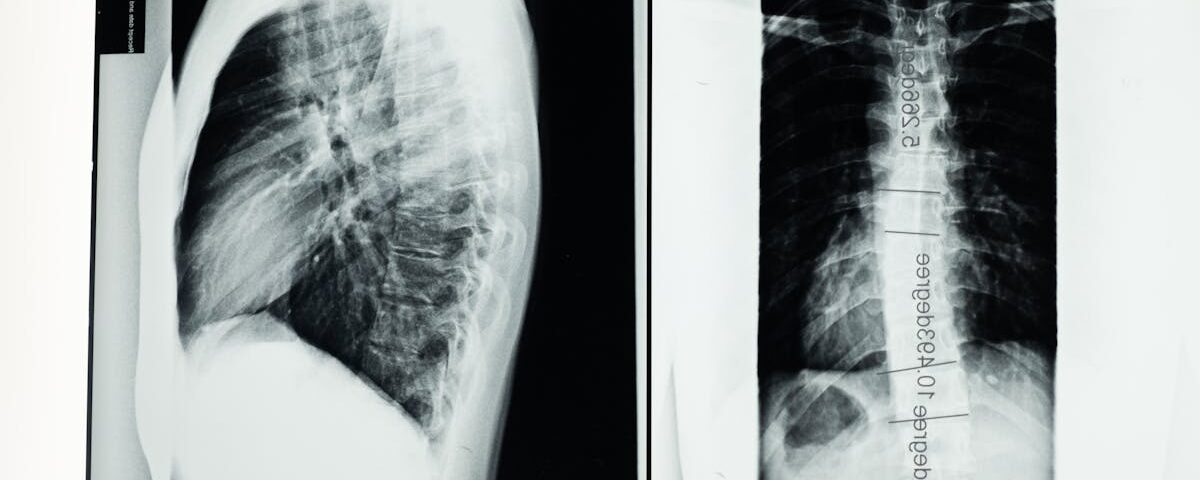

Comment diagnostiquer correctement la brachialgie?

Un examen clinique, combiné à une imagerie médicale comme une IRM, est nécessaire pour un diagnostic précis.